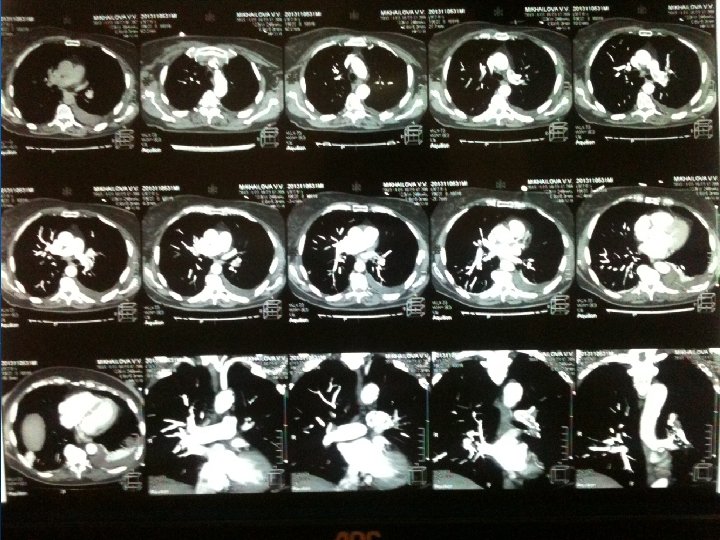

Проведен комплекс лабораторных и диагностических мероприятий n n n n общий анализ крови (Нв – 91 г/л) общий анализ мочи биохимический анализ крови + электролиты (Общий белок – 59 г/л) газовый состав крови ( Pa. CO 2 -30, 4, Pa. O 2 – 58, 3) Коагулограмма (МНО - 1, 18, АЧТВ – 25, 3, тромбоциты – 193*10/л) ЭКГ рентгенограмма органов грудной полости КТ-головы, груди

Диагноз: Основное заболевание: Тяжелая сочетанная травма головы, груди. ОЧМТ. Линейный перлом чешуи затылочной кости слева с переходом на чешую левой височной кости и на основание черепа( левую пирамиду). Перелом клиновидной кости. Ушиб головного мозга средней степени тяжести с формированием контузионных очагов в правых лобной, височной, теменной зонах, левом таламусе. САК. Ушитая рана левой теменной области. Закрытая травма груди. Множественные переломы ребер. Ушиб обоих легких. Двусторонний гидроторакс. Осложнения: Острая дыхательная недостаточность 2 ст. Сопутствующая патология: Ишемическая болезнь сердца. Атеросклероз коронарных сосудов. Гипертоническая болезнь 2 ст.

На 8 -е сутки внезапное возникновение симптомов дыхательной недостаточности: n n n ТАХИПНОЭ ДО 35 -37 в минуту ОДЫШКА ЦИАНОЗ ГУБ БЛЕДНОСТЬ КОЖНЫХ ПОКРОВОВ СНИЖЕНИЕ САТУРАЦИИ ДО 88% ТАХИКАРДИЯ (ЧСС – 105 в мин)

Дифференциальная диагностика n n n пневмония ателектаз пневмоторакс гемоторакс ТЭЛА